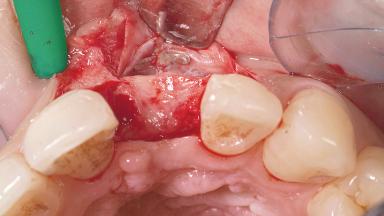

A 30-year-old female patient had lost tooth 21 and was referred to our clinic for consultation and treatment. Due to advanced apical infection, tooth 21 had been extracted two months earlier at another clinic and an acrylic-resin tooth had been bonded to the adjacent teeth. The patient desired implant treatment to avoid any damage to the adjacent natural teeth. While the patient had no history of any systemic disorder, she was a heavy smoker and exhibited medium to advanced periodontitis in the entire jaw. After the initial treatment to achieve a pocket probing depth of less than 4 mm and no bleeding on probing, a decrease in the height of the papillae mesial and distal to the extraction site and overall gingival recession were observed.

Bone Augmentation Horizontal|Staged

Augmentation Materials Autogenous chips|Membrane

Soft Tissue Anatomy Intact Defective

Bone Volume Horizontally and vertically sufficient Horizontally deficient Deficient vertically or deficient vertically AND horizontally

Bone Volume Deficient horizontally, requiring prior grafting